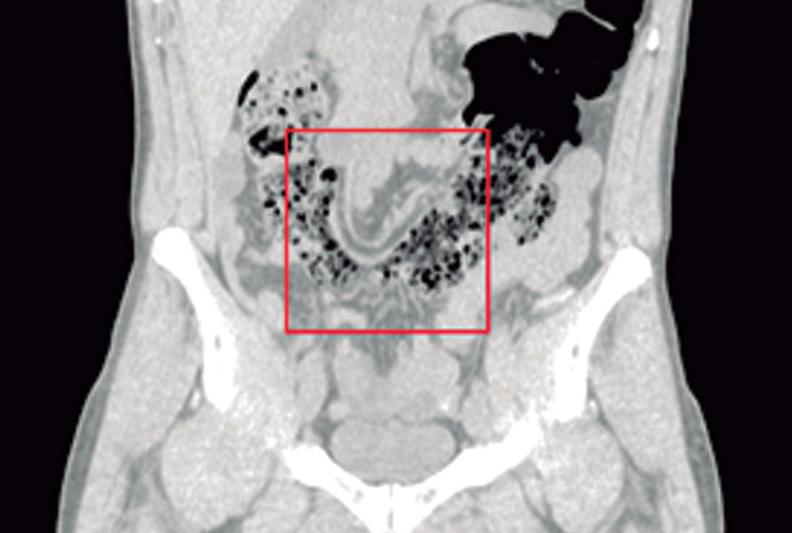

CASOS CLÍNICOS Coexistencia de cáncer de colon y malrotación intestinal: un raro desafío anatómico y oncológico

Nicolás Lavorato, Alejandro Moreira Grecco, Tomás Flores, Rodrigo Morales, Gonzalo Hugo Zapata, Luis Ernesto

Sarotto

Nicolás Lavorato, Alejandro Moreira Grecco, Tomás Flores, Rodrigo Morales, Gonzalo Hugo Zapata, Luis Ernesto Sarotto